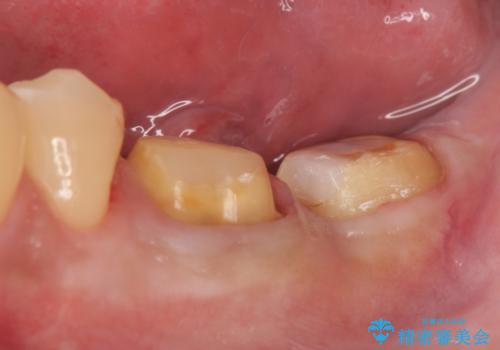

左下に被せ物を被せるクリアランス(補綴のための上下のスペース)ないため、十分な歯冠長を確保するため歯冠長延長術を行いました。

その後歯肉の回復を待ち、フルジルコニアクラウンにて補綴を行いました。

歯冠長延長術とは歯肉弁根尖側移動術とも言い、歯の高さが低くクラウン(被せ物)による治療が難しい場合に、歯茎を歯根方向に下げることで歯の高さを確保する手術です。歯の高さが十分にあることで、外れにくいしっかりとしたクラウンを被せることができます。